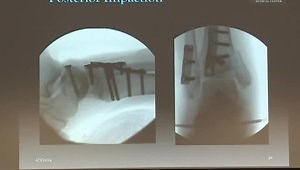

Fracture - Tibial Pilon Fracture

Fracture - Pilon Fracture